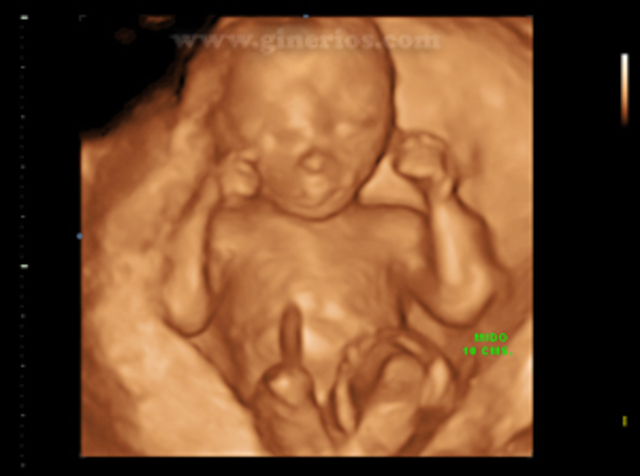

• 9ª Semana

9ª Semana

Corporalmente, se diferencia el sexo.

• 16ª semana

16ª semana

El feto se mueve en el líquido amniótico y la madre puede sentir los movimientos. También oye ruidos y percibe la luz a través de las membranas de los párpados.